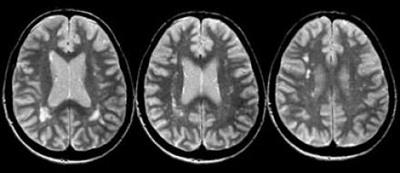

МРТ превосходит другие анализы при рассеянном склерозе по информативности, являясь «золотым» стандартом диагностики. При проведении аппаратного исследования можно определить расширение полости мозговых желудочков и атрофию коры.

Чтобы получить качественный снимок, при проведении МРТ используют парамагнитную контрастную жидкость. В участках подвергшихся разрушению миелина накопление специального вещества происходит активнее. Высокоточный способ позволяет увидеть мельчайшие дефекты в белом веществе нервной ткани. Диагноз при проведении МРТ устанавливается при обнаружении не менее 4 участков демиелинизации размером более 3 мм, из которых хотя бы один должен располагаться около мозговых желудочков (перивентрикулярно).